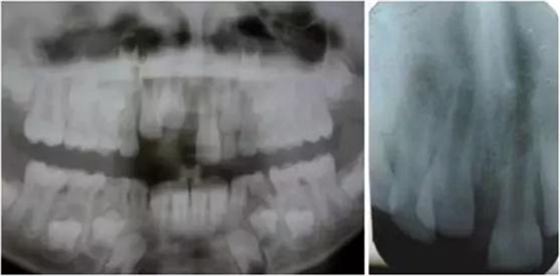

影像學(xué)檢查:根尖片以及全景片(圖2)提示牙槽骨骨折,根尖挫入至唇側(cè)骨板或鼻底。根尖片提示牙11,12 和21根尖發(fā)育不完全,呈喇叭口狀。受累牙的根管壁薄且不完全成形(圖2)。牙片顯示沒(méi)有冠折和根折。

( 圖2)